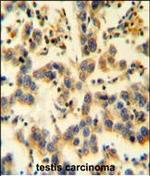

KIAA0090 Polyclonal Antibody

WB IHC (P) Flow